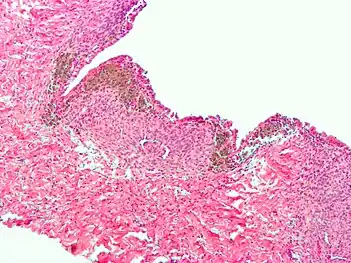

Endometriosis, abdominal wall

Micrograph of the wall of an endometrioma. All features of endometriosis are present (endometrial glands, endometrial stroma and hemosiderin-laden macrophages).